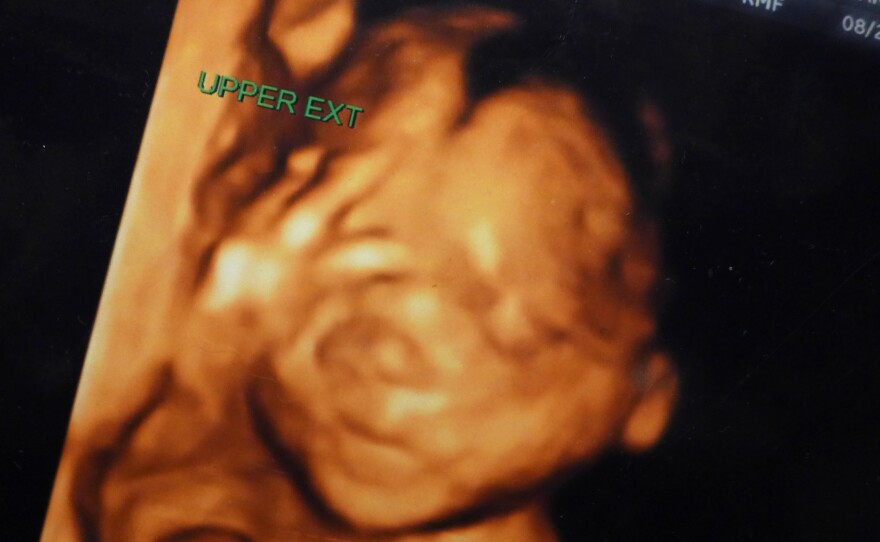

Mojica is waiting to meet her son, who so far she has seen only in pixels of black and shades of orange. The ultrasound image shows the outline of a human face with his eyes closed directly facing the camera. It appears modulated, akin to a half finished piece of pottery. The five stubby fingers of his right hand are pressed against his forehead as if he is lost in contemplation.